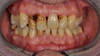

Restauration complète maxillaire et mandibulaire

Restaurations par couronnes céramo-céramiques